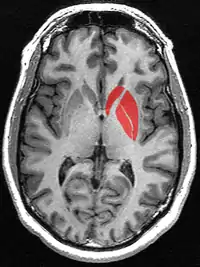

Смугасте тіло (лат. corpus striatum) - підкіркове утворення переднього мозку і надзвичайно важливий компонент екстрапірамідної системи й системи винагород (англ. Reward System), яке отримує глутамінергічні та дофамінергічні імпульси з різних структур і служить вхідними воротами імпульсів до решти системи базальних гангліїв. У всіх приматів волокнами білої речовини, які називають внутрішньою капсулою, дорзальна частина смугастого тіла ділиться на дві частини, які називаються хвостате ядро і сочевицеподібне ядро. Вентральна частина складається з прилеглого ядра і нюхового горбка. Смугасте тіло координує декілька когнітивних функцій, включаючи рухи й їхнє планування, прийняття рішень, мотивації, підкріплення й винагороду.

Смугасте тіло поділяється на дорзальну й вентральну частини відповідно до анатомічного розташування і функціональних зв'язків. Вентральний стріатум складається з прилеглого ядра і нюхового горбка, в 'дорсальний стріатум входять хвостате ядро і лушпина.

Анімоване зображення смугастого тіла

Смугасте тіло. Пряма й бокова проекції